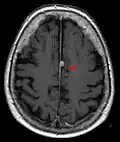

Typische randständige Lokalisation eines Meningeoms rechts (Kernspintomographie, T1-gewichtet mit Kontrastmittel) -